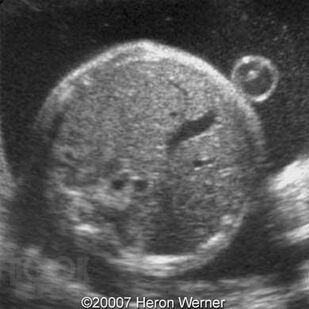

Врождённые аномалии желудочно-кишечного тракта у детей

Учебное пособие полностью соответствуют требованиям ФГОС ВО (2020). Данное учебное пособие посвящено вопросам клиники, ранней диагностики и лечения врождённых аномалии желудочно-кишечного тракта у детей. Учебный материал адаптирован к образовательным технологиям с учетом специфики обучения на педиатрическом и лечебном факультете. Пособие иллюстрировано рисунками и рентгенограммами, имеются ситуационные задачи и тестовые задания.